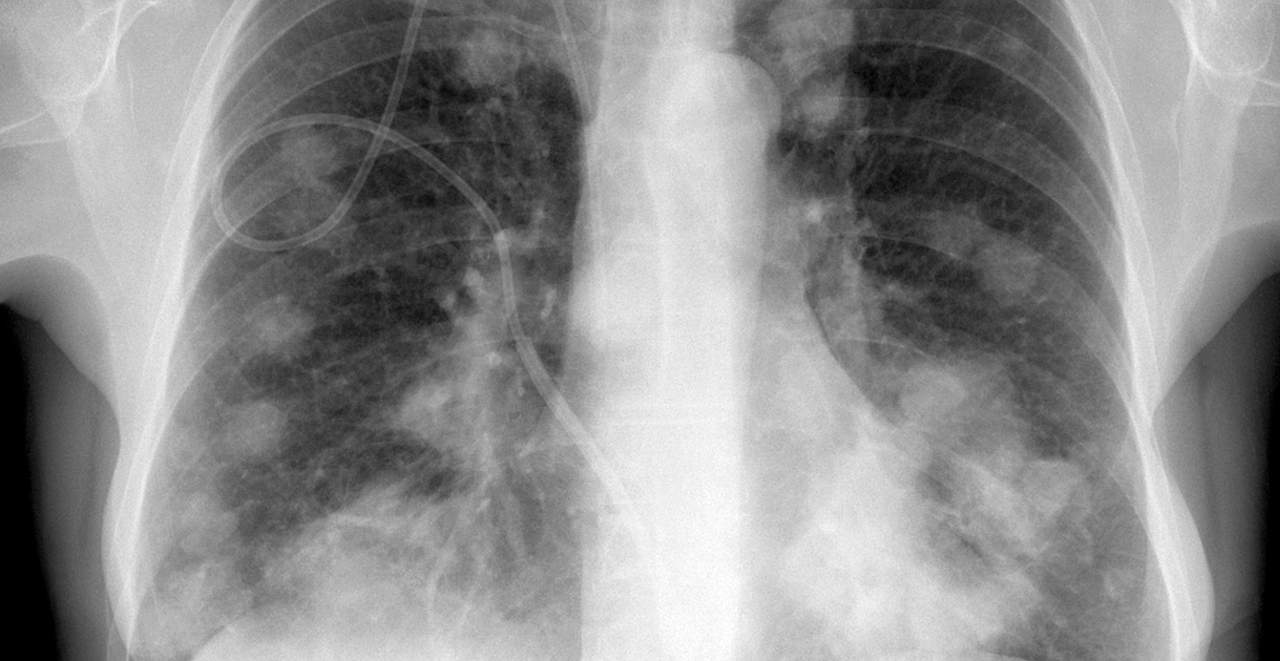

Meer dan de helft van de kankerpatiënten bij wie de kwaadaardige cellen van de tumor zich verder verspreiden, heeft uitzaaiingen in de longen. Leuvense onderzoekers hebben ontdekt hoe dat komt.